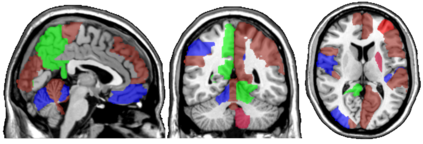

In this paper, we propose methods for functional predictor selection and the estimation of smooth functional coefficients simultaneously in a scalar-on-function regression problem under high-dimensional multivariate functional data setting. In particular, we develop two methods for functional group-sparse regression under a generic Hilbert space of infinite dimension. We show the convergence of algorithms and the consistency of the estimation and the selection (oracle property) under infinite-dimensional Hilbert spaces. Simulation studies show the effectiveness of the methods in both the selection and the estimation of functional coefficients. The applications to the functional magnetic resonance imaging (fMRI) reveal the regions of the human brain related to ADHD and IQ.